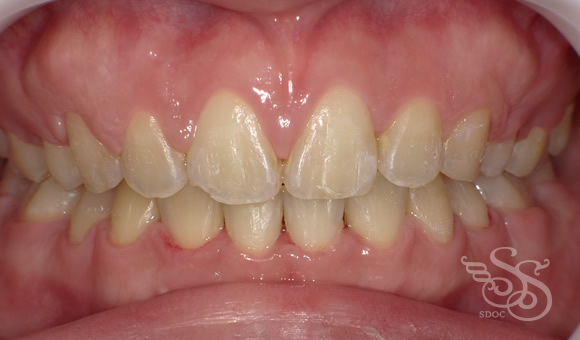

正面:術後

歯ならびだけでなく

口もとの前突感もなくなり

素敵な口もとになりました。